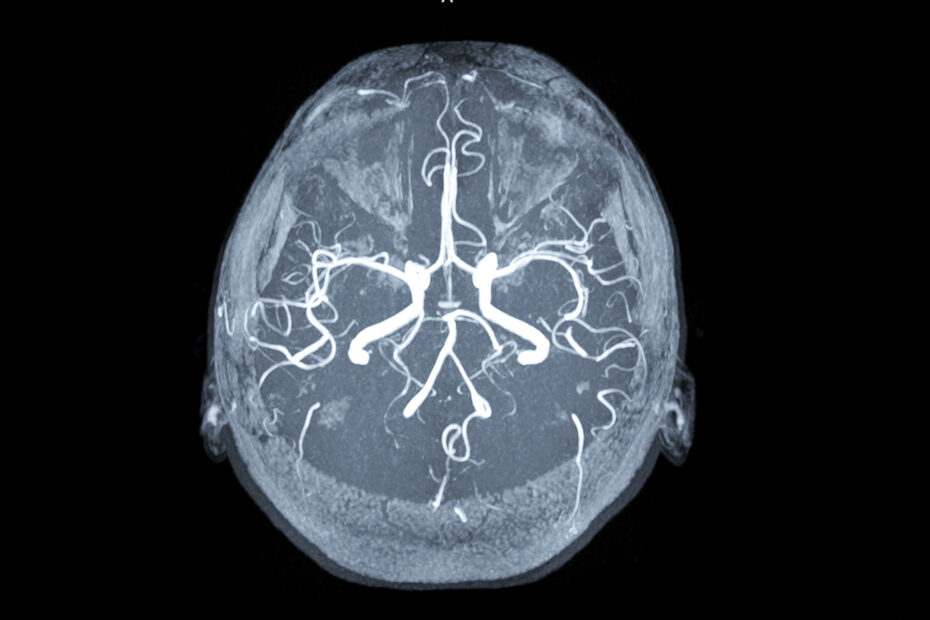

L’angiografia cerebrale è un esame diagnostico mininvasivo che consente di visualizzare in modo dettagliato i vasi arteriosi e venosi del cervello.

A differenza di altri esami di imaging, l’angiografia cerebrale permette una mappatura precisa e dinamica della circolazione intracranica, risultando indispensabile sia in fase diagnostica sia nella pianificazione di trattamenti endovascolari.

Le immagini vengono acquisite in sequenza rapida, in proiezioni multiple e con tecniche digitali (DSA – Digital Subtraction Angiography) che eliminano i dettagli ossei per una visione nitida del sistema vascolare cerebrale.

L’angiografia cerebrale fornisce immagini ad alta risoluzione che mostrano:

- il decorso e il calibro delle arterie cerebrali (carotide interna, cerebrale media, anteriore, posteriore, vertebrale e basilare);

- la presenza di dilatazioni anomale (aneurismi);

- anomalie del circolo venoso cerebrale;

- shunt artero-venosi patologici, tipici di MAV e fistole;

- zone ischemiche o a flusso ridotto, con possibilità di valutazione dinamica del circolo collaterale.

Grazie alla possibilità di iniettare selettivamente il mezzo di contrasto, l’angiografia consente un’analisi localizzata anche su singoli rami vascolari, cosa non possibile con altre metodiche.